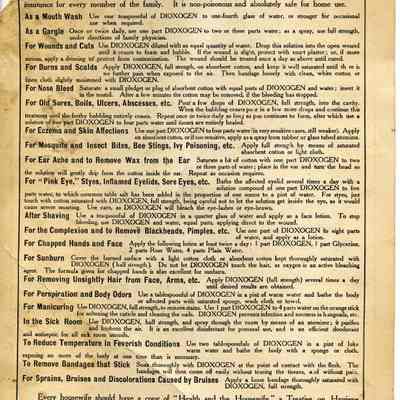

AFH Bayonet with Black Handle Ad, Magazine

Ad, Magazine Ad, Magazine

Ad, Magazine Ad, Magazine

Ad, Magazine Ad, Magazine

Ad, Magazine Ad, Magazine

Ad, Magazine Ad, Magazine

Ad, Magazine Ad, Magazine

Ad, Magazine Ad, Magazine

Ad, Magazine Ad, Magazine

Ad, Magazine Ad, Magazine

Ad, Magazine Ad, Magazine

Ad, Magazine Ad, Magazine

Ad, Magazine Ad, Magazine

Ad, Magazine Ad, Magazine

Ad, Magazine Ad, Magazine

Ad, Magazine Ad, Magazine

Ad, Magazine Ad, Magazine

Ad, Magazine Ad, Magazine

Ad, Magazine Ad, Magazine

Ad, Magazine Ad, Magazine

Ad, Magazine Ad, Magazine

Ad, Magazine Ad, Magazine

Ad, Magazine Ad, Magazine

Ad, Magazine Ad, Magazine

Ad, Magazine Ad, Magazine

Ad, Magazine Ad, Magazine

Ad, Magazine Ad, Magazine

Ad, Magazine Ad, Magazine

Ad, Magazine Ad, Magazine

Ad, Magazine Ad, Magazine

Ad, Magazine Ad, Newspaper